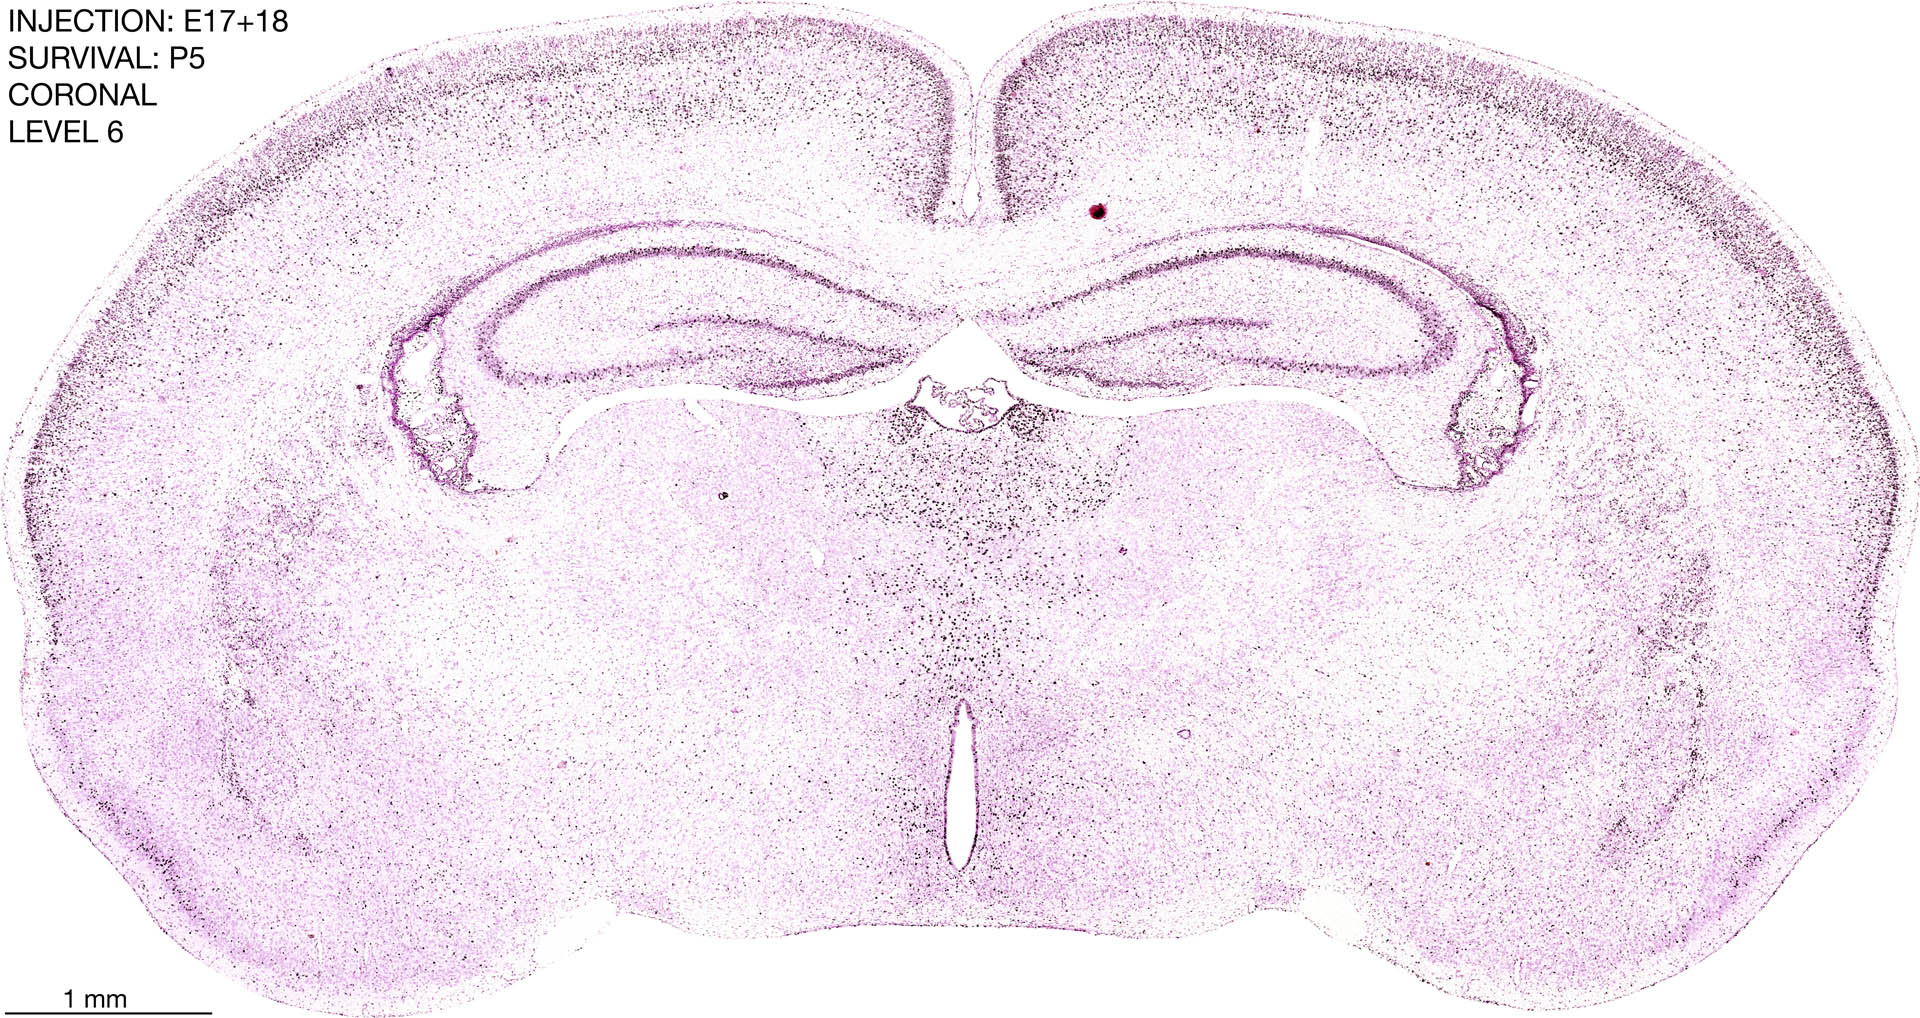

E17+18 P5 Survival The images below are from the brain of a rat that was exposed to tritiated thymidine on E17+18 and survived to P5. Download: Large | High Res Download: Large | High Res Download: Large | High Res Download: Large | High Res Download: Large | High Res Download: Large | High Res Download: Large | High Res Download: Large | High Res Download: Large | High Res Download: Large | High Res Download: Large | High Res Download: Large | High Res Download: Large | High Res Download: Large | High Res Download: Large | High Res Download: Large | High Res Download: Large | High Res Download: Large | High Res Download: Large | High Res Download: Large | High Res Download: Large | High Res Download: Large | High Res Download: Large | High Res Download: Large | High Res Download: Large | High Res Download: Large | High Res